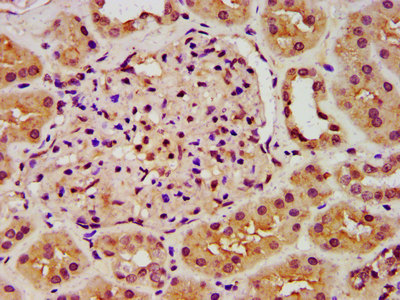

The image on the left is immunohistochemistry of paraffin-embedded Human cervical cancer tissue using CSB-PA981926(ANK3 Antibody) at dilution 1/50, on the right is treated with synthetic peptide. (Original magnification: x200)